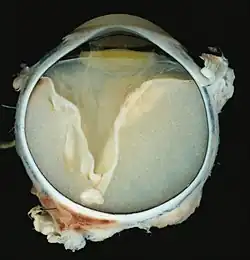

A case of Coats' disease, showing total retinal detachment with subretinal exudate containing cholesterol crystals and a fibrous nodule in the posterior pole

Grossly, retinal detachment and yellowish subretinal exudate containing cholesterol crystals are commonly seen.